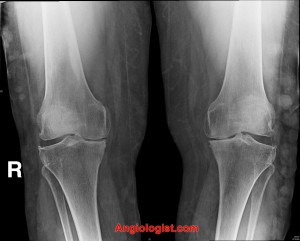

Other, less commonly utilized imaging studies that may demonstrate varicose veins include plain radiographs and CT scan imaging, as shown in the following pictures: